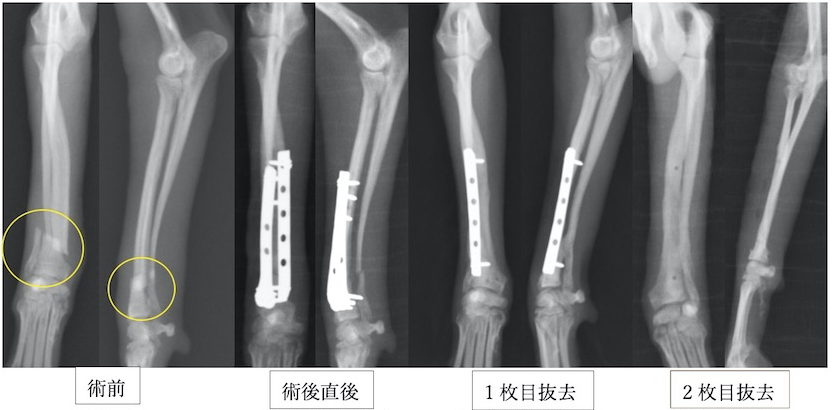

次の症例は以前の骨折を他院にてプレート固定していたそうですが、ある時からまた足を上げるとのことで来院しました。矢印の部分で折れてしまっています。

入っていたプレートを抜去したところです。入っていたところの遠位(左写真の左側)に骨折線があります。プレートのスクリューホールに骨が入り込むのでボコボコとした形になります。

今回の手術後の写真です。非常に長いプレートが入っているのは、手術して再骨折があった場合にはもとのプレートよりも長いプレートを入れる必要があるからです。また、骨が痩せて細くなっているケースが多いので術後も注意が必要です。

術後レントゲンです。橈骨全域に渡ってプレートが入っています。近位は少し外側に曲がっているため、最初からプレートを曲げています。術後2日目には患肢を使っての歩行が可能でした。また、キャスト(ギプス)も使わないので、ストレスなく生活が可能です。術後1ヶ月半ほどで正面のプレートを抜去しています。

この子もプレートが破綻して2回めの手術をしているため、プレートが長くなっています。

術後経過は順調で2ヶ月ほどで正面のプレートを抜去しました。